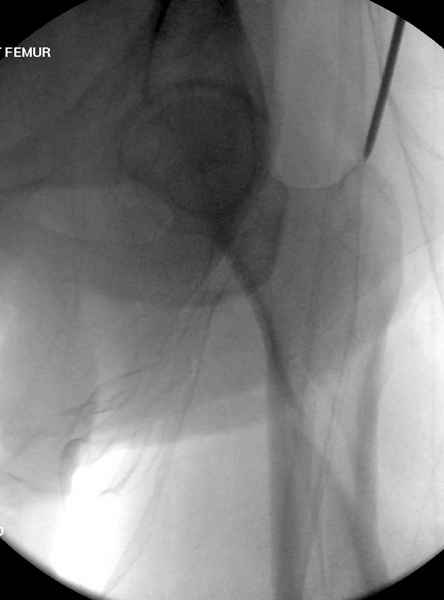

Учитывая, что случай ургентный, больной поступил вечером, не стали делать вытяжение и срочно провели операцию по фиксации перелома бедра антеградным штифтом Versa Nail от DePuy.

Для профилактики дальнейшего раскола в шейке предварительно во время проксимального рассверливания спереди и сзади провели временные спицы, которые в дальнейшем были заменены на шурупы (miss nail method)